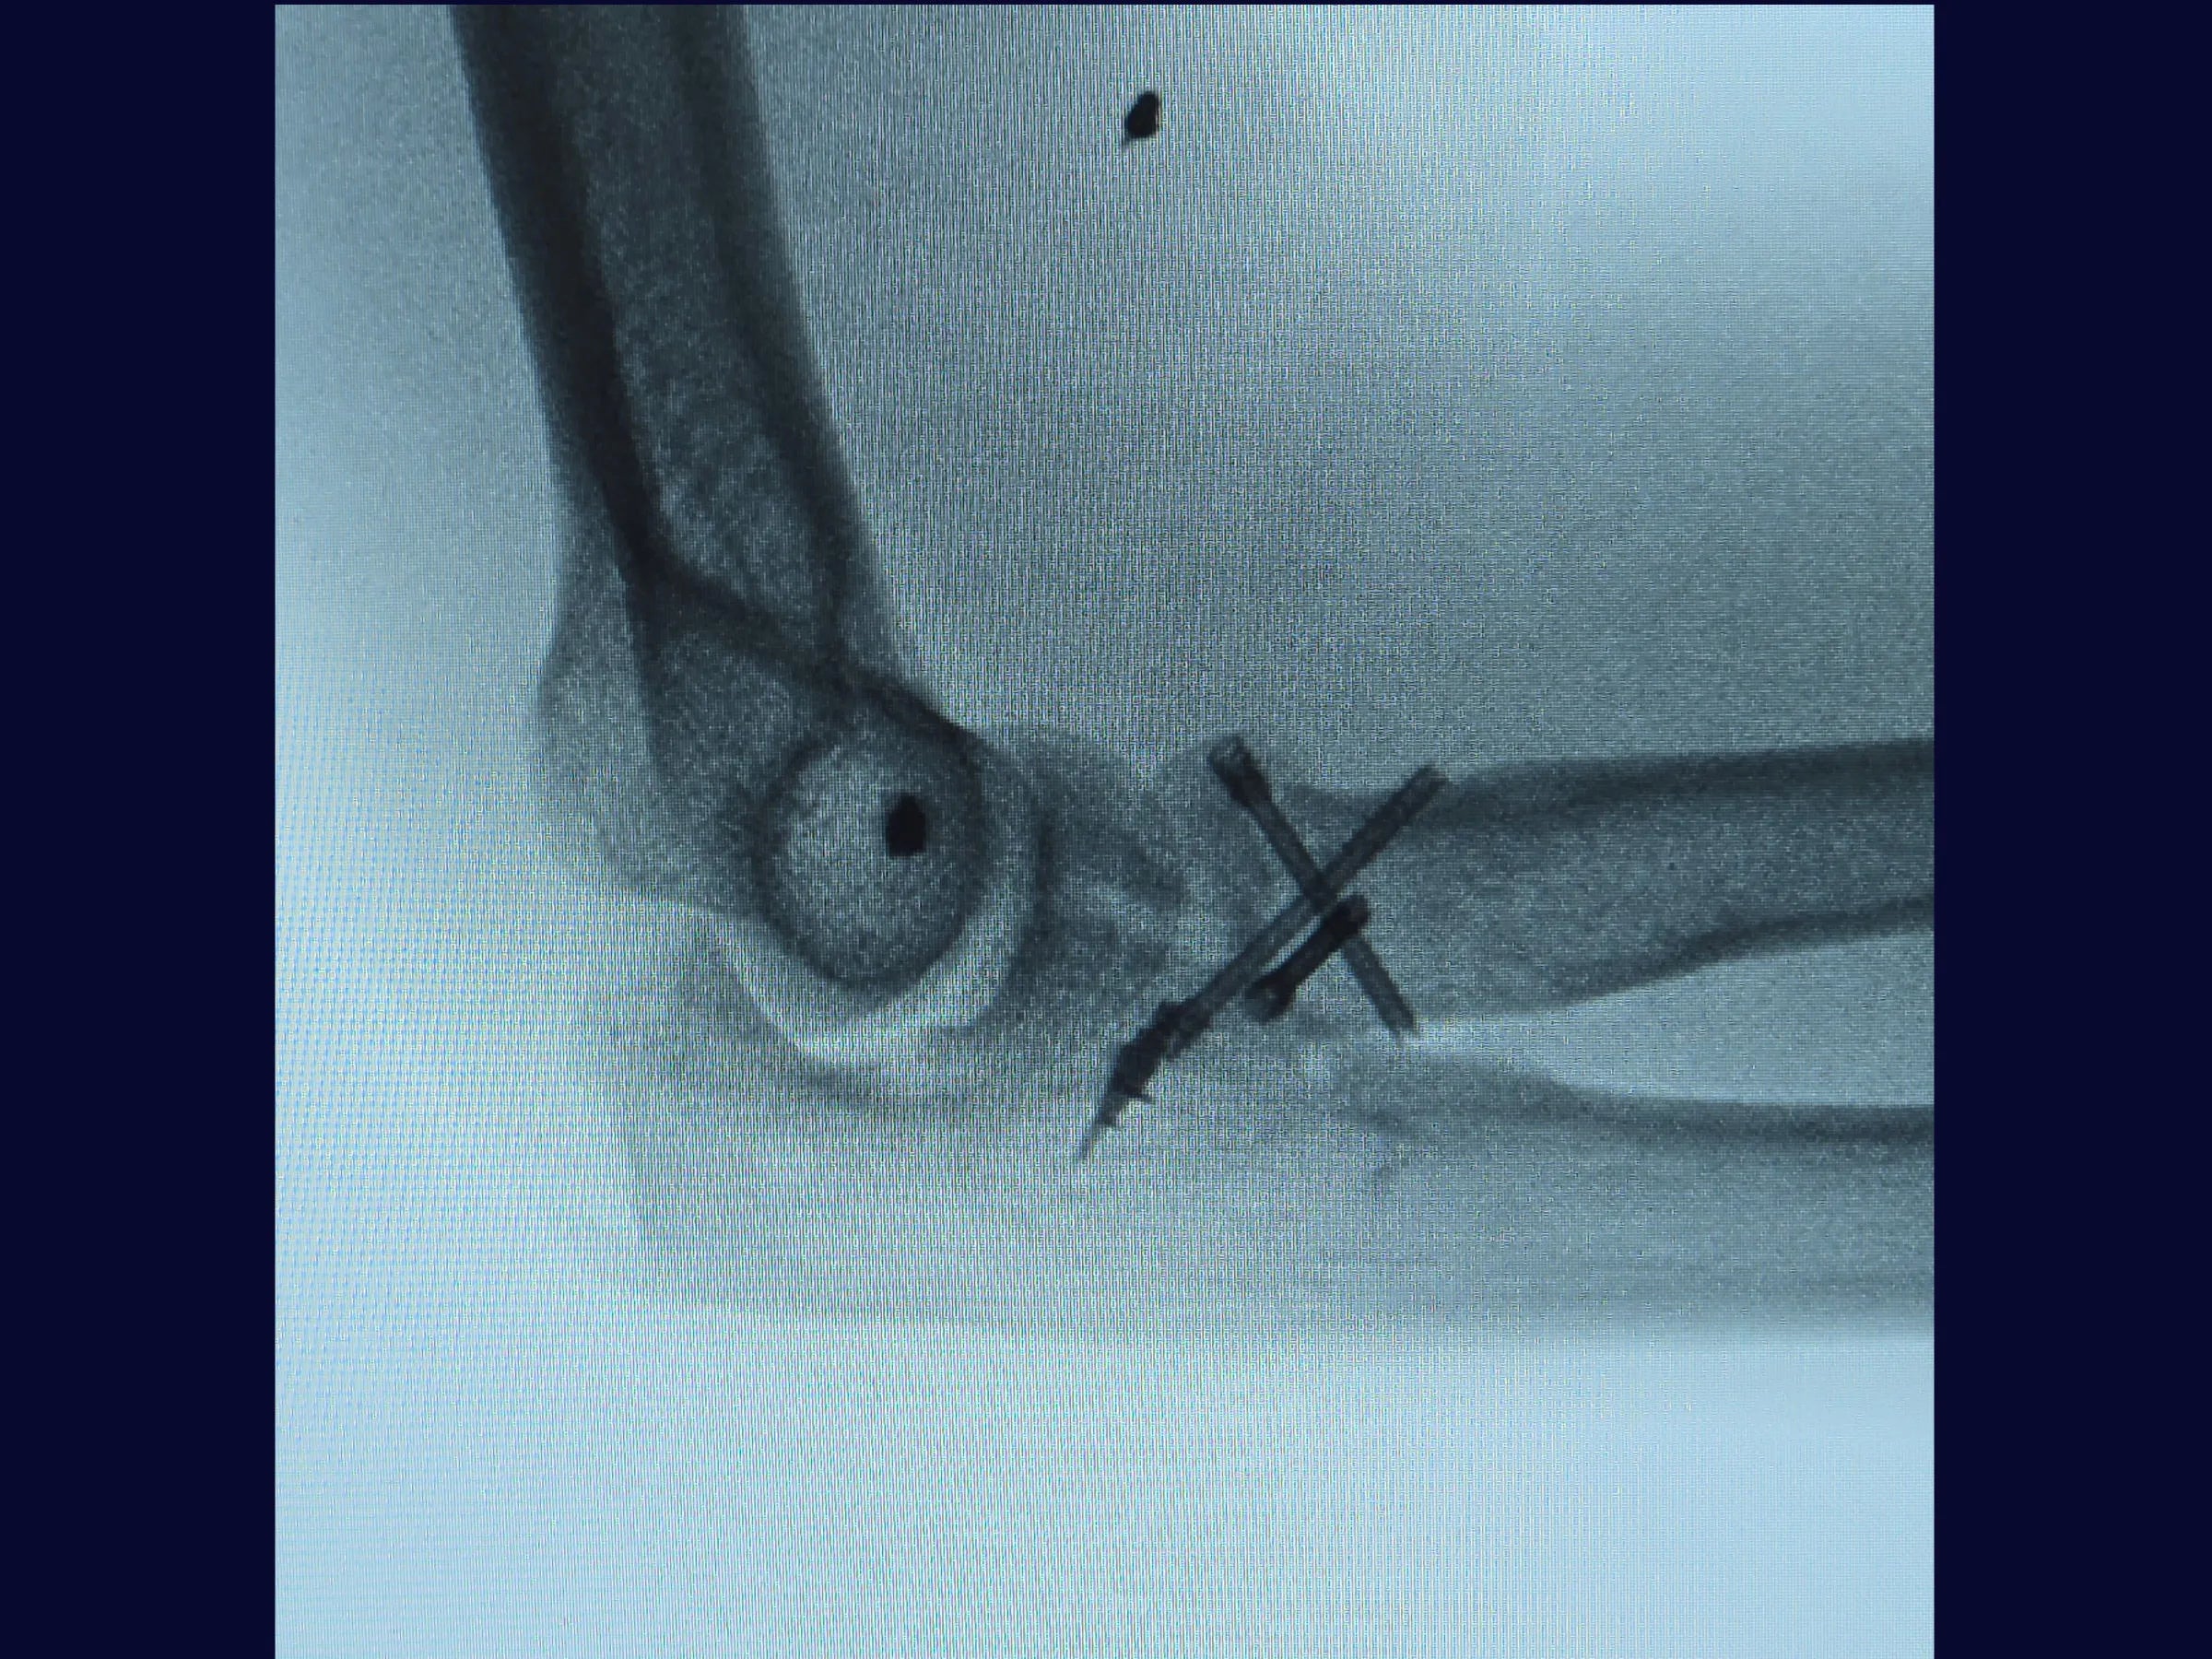

Este treinamento apresenta a técnica do tripé com parafusos de dupla compressão e reinserção capsular com âncora metálica, em vídeo 4K sob a perspectiva cirúrgica, permitindo compreender cada detalhe técnico e aplicar com segurança na prática.

- Técnica do tripé com parafusos de dupla compressão (2,4 mm).

- Testes de estabilidade intraoperatória e mobilidade precoce.

- Fixação Segura: Parafusos sepultados em ângulo biomecânico de 45°.